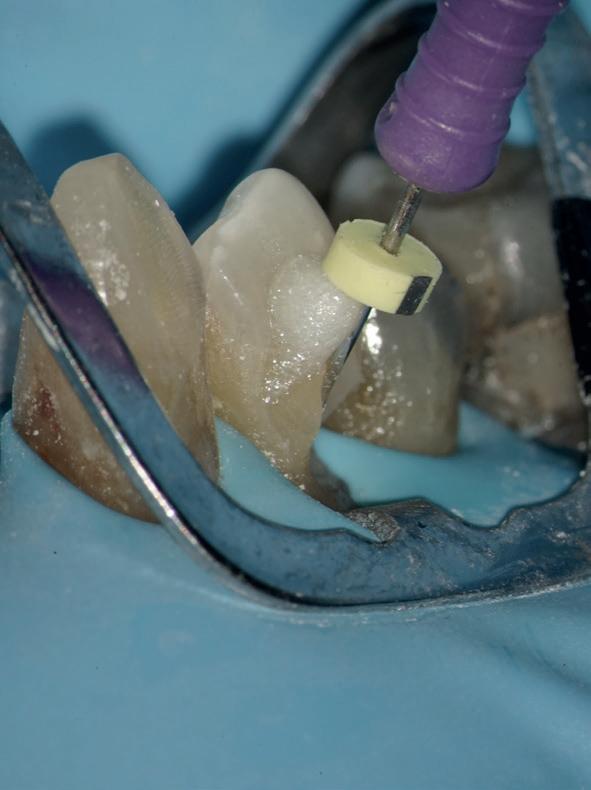

Stap 5: Teflon aanbrengen

Pak één centimeter Teflon tape en prop dit aan de tegenoverstaande zijde van waar de wig zich bevindt. Je doet dit met een bij de punt platgeslepen Sikkelsonde. Gebruik van Teflon tape zorgt voor een perfecte adaptatie en afsluiting van de matrixband, zelfs bij furcaties (afbeelding 8 en 9).

Stap 6: Vullen

Zorg ervoor dat je allereerst de bodem en opstaande wanden van de preparatie vult, zodat je met een Ash 49 de matrixband mooi tegen het buurelement kan forceren. Als de knobbels genoeg ‘body’ hebben, kan de separatiering geplaatst worden voor een mooi contactpunt (afbeelding 10).